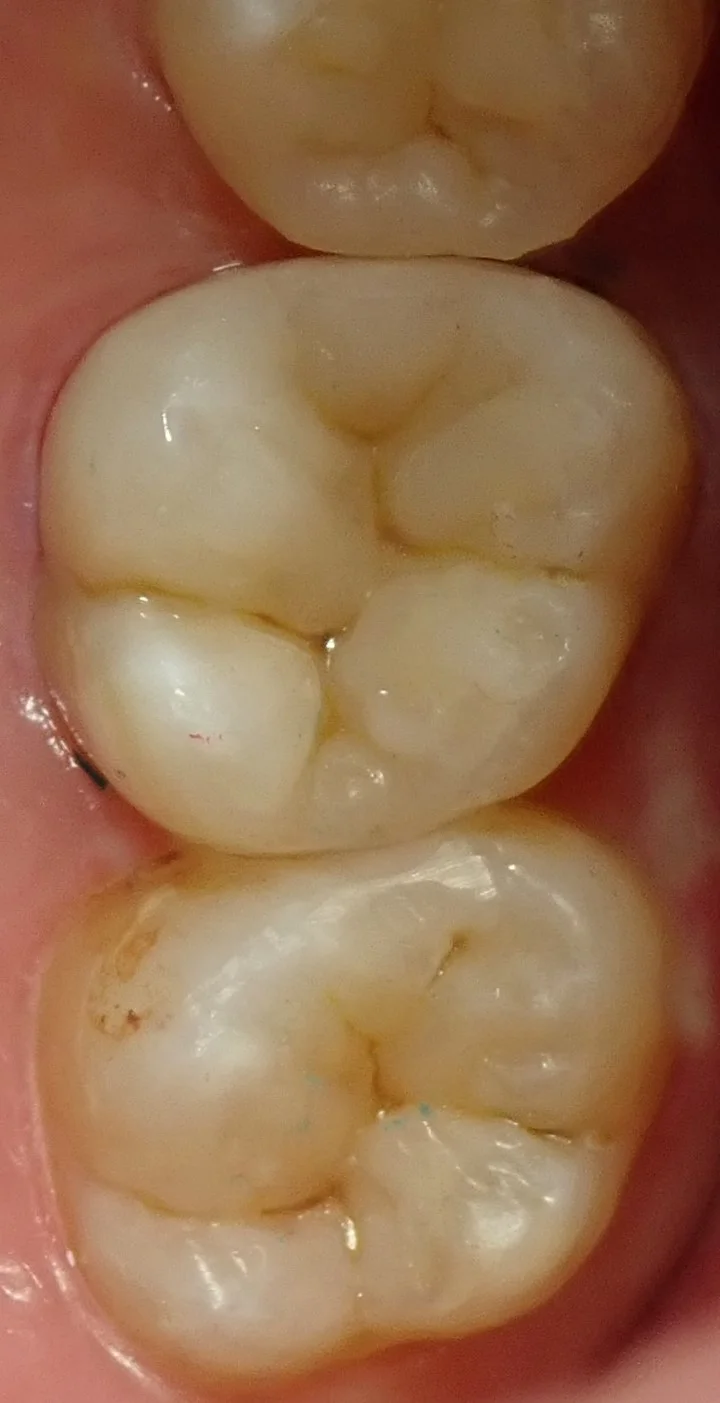

そして、充填終了後の画像がこちらです。

ある程度自然な仕上がりに出来たかと思います。

よく仕上がった写真を他の歯科医師の方にお見せして、治療したところはどこだ!って言ってたりするんですが、ピンポイントで言い当てられたことはあまりないので、プロの目も誤魔化せてるってのは結構嬉しいですね。

フロスなどでも引っ掛からないように仕上げてますので、そのまましっかりと使っていただけるかと思います。